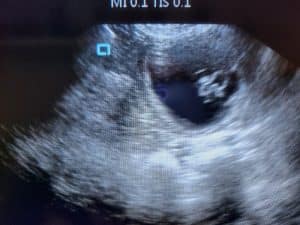

• Confirmation ultrasound scan at day 30 from second mating.

• A peace of mind ultrasound scan around day 40-45

Pet Ultrasound Scanning.

1 scan at our premises – £35

1 scan at your location – from £40 (depending on location)

Emergency scans in hours as above, out of hours varies

• Confirmation scan at day 30 from second mating.

• Peace of mind scan at around day 40-45.